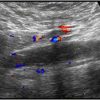

Huyết khối TM chủ dưới

Huyết khối TM chủ dưới - Ảnh 2

» Thông tin: Nữ giới – 68 tuổi.

» Lâm sàng: Sưng phù chi dưới.